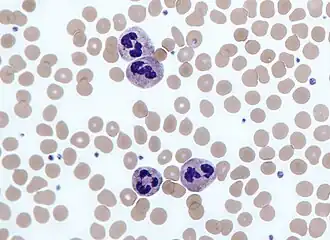

Circular thresholding is an algorithm for automatic image threshold selection in image processing. Most threshold selection algorithms assume that the values (e.g. intensities) lie on a linear scale. However, some quantities such as hue and orientation are a circular quantity, and therefore require circular thresholding algorithms. The example shows that the standard linear version of Otsu's method when applied to the hue channel of an image of blood cells fails to correctly segment the large white blood cells (leukocytes). In contrast the white blood cells are correctly segmented by the circular version of Otsu's method.